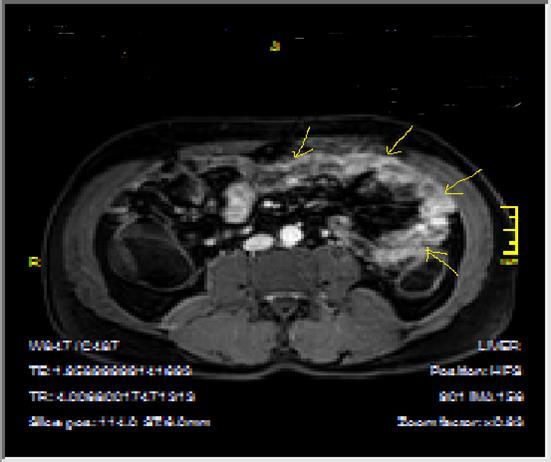

Figure 3a-3b-3c.Diffuse mucosal involvement and extreme luminal narrowing in the terminal ileum due to Crohn’s disease on T2W coronal sequence after OCA administration, stricture and string sign near ileo-ceccal valve in Figure 3b.